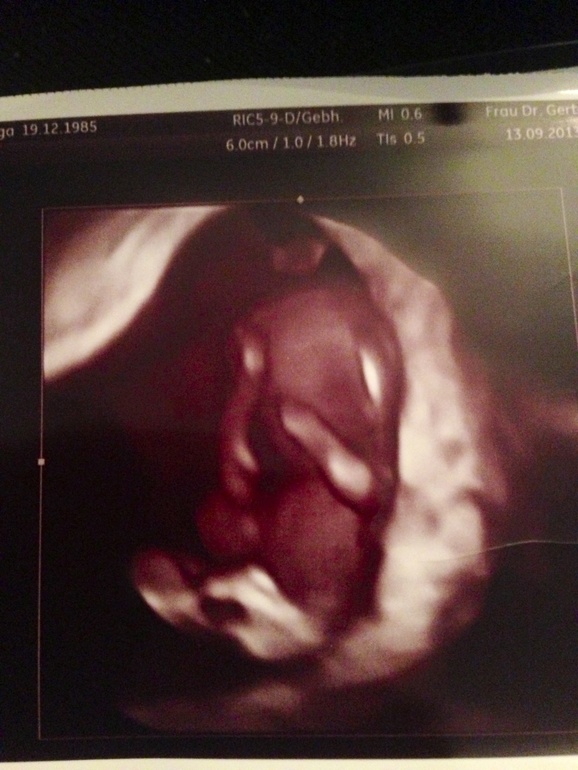

Результаты: УЗИ, КТГ, доплера, скринингаСходили мы на плановое УЗИ. Опять же много много эмоций, муж в предвкушении. И вот показывают нам наше чудо.Сидит скрестив ноги по-турецки, поднимаетто одну ручку, то другую вверх и двигает попкой. Танцует!!!! Потом видимо неприятно ему стало и он закрыл личико ручками, это так здорово. Для скриннинга мы еще малявки, 26 сентября пойдем снова меряться.Врачом я очень довольна и в 4 Д мне показала и так. Сдала кровь, посмотрим что с моим ттг. Вот так мы посмотрели на наше чудо , ну и маленький фотоотчет.

Mne besplatno vse delajut i foto i UZI. Voobshe u nas 3 besplatnyx uzi, no moja G govorit, chto budet delat stolko, skolko nado. Smotrela, ona smotrela i govorit, mozhno i 4D posmotret i vkljuchila nam. I vot 2 fotki sdelala. No tak prikolno nabljudat za nim. :))))